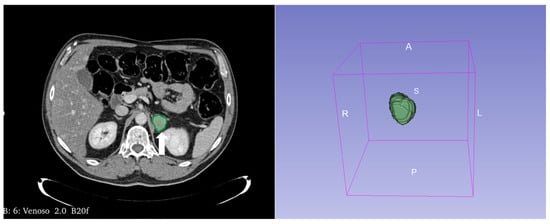

Figure 3.

60-year-old woman with history of breast cancer and adrenal metastasis. Left adrenal mass with inhomogeneous enhancement (arrow) on CT portal phase in axial (A) and coronal (B) planes, and positive PET (C).